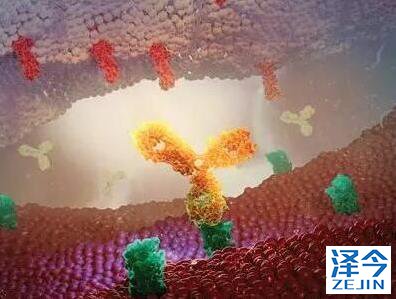

泰瑞沙(AZD9291)是一种不可逆的选择性EGFR突变抑制剂,它源自科学家对肿瘤耐药机制的深入探索,能对由于T790M突变引起的肿瘤耐药产生精准抑制。